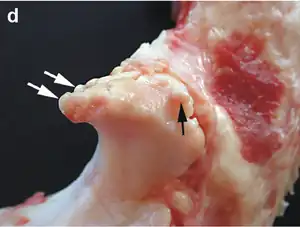

| Small marginal osteophytes (arrows) of the processus anconeus of the ulna can be seen in this gross pathological specimen of a sow. | |